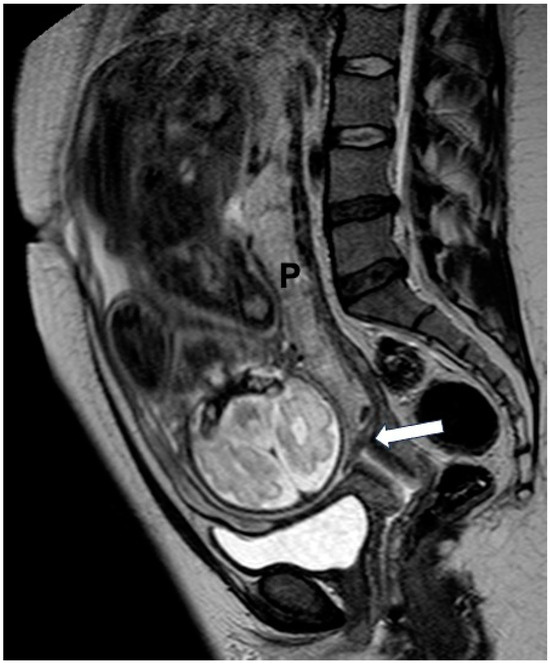

2.2. MRI Protocol

2.3. Image Interpretation